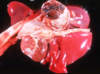

Q

This is the stomach of a horse. What lesion is shown here?

A

equine gastric ulceration